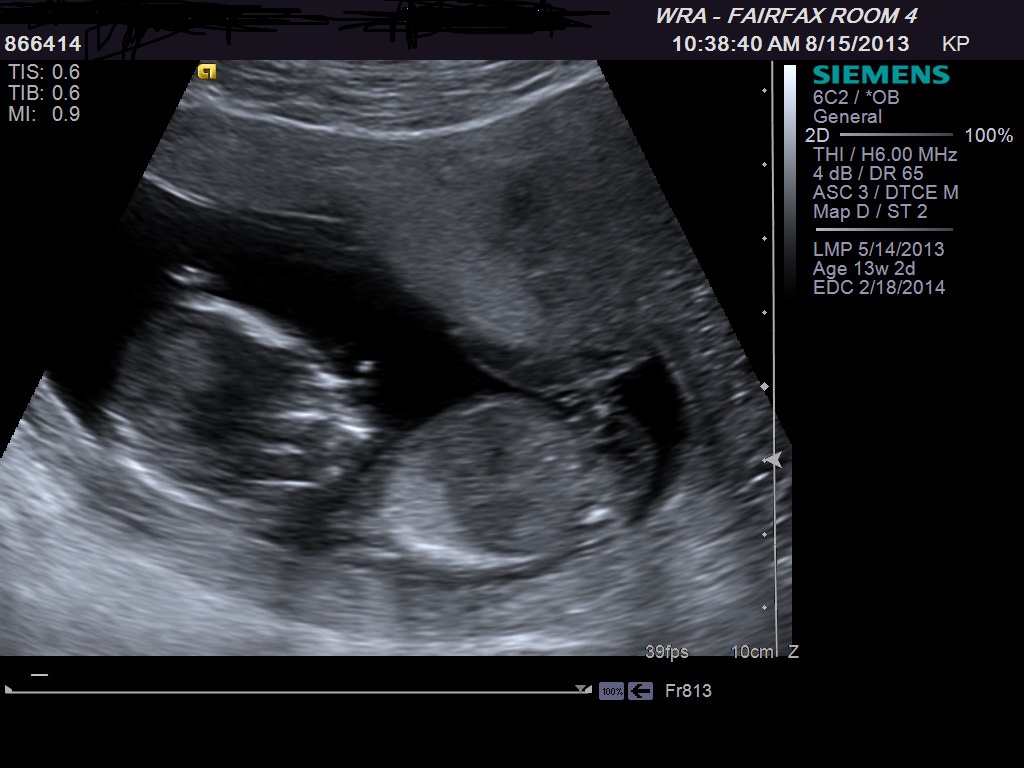

Attachment 13972Attachment 13971Attachment 13970U/S on Monday any last guesses

Maybe boy. The first pic shows what may be a boy bump but not totally clear that's what it is.

possibly boy based off first image.The other two images look more girly but to be honest, i am not sure if that is the nub there as baby is not completely side on

Ok, confused... The last one I think looks like a girl :confused:

I am 50/50. The nub doesn't look boy or girl to me but inbetween. Sorry x